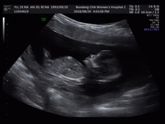

Второе УЗИ ?

За две недели заметно подросли 8-9 неделя ❤️ наше чудо ❤️